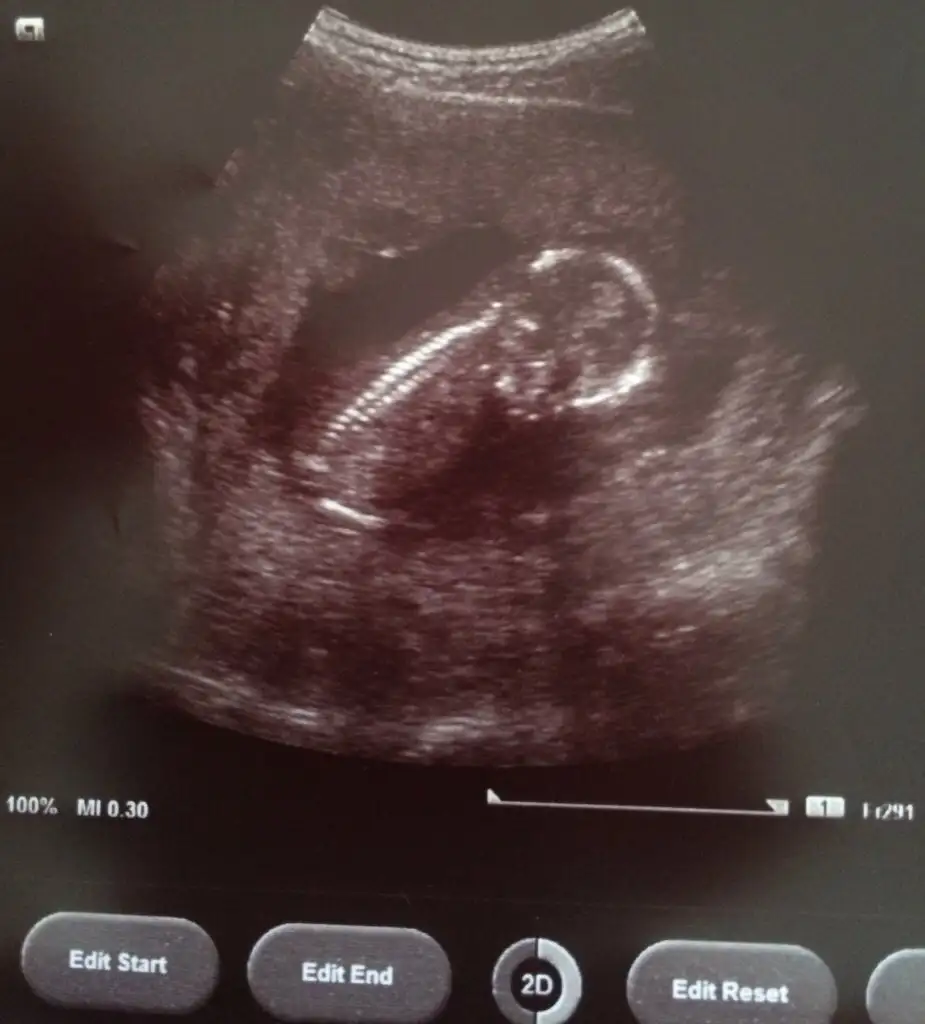

Daha 9+4üz ama var mı tahmin çok merak ediyorum